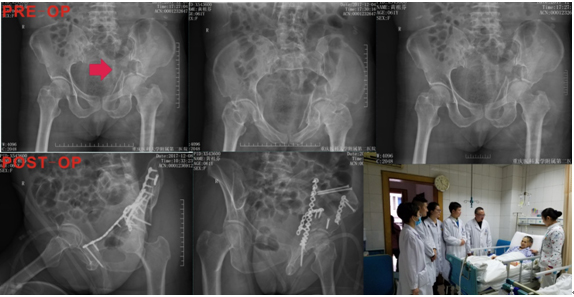

患者黄某某,女,61岁,因“车祸致左髋疼痛、意识障碍3小时”入院。X片及CT提示:蛛网膜下腔出血,骨盆左侧粉碎性骨折包括左侧髂骨、左侧耻骨上下支骨折,以及左侧髋臼骨折,双侧多发肋骨骨折,急性创伤性肺损伤,左肾及胰腺损伤。患者年龄大,全身多脏器损伤,其中左侧髋臼双柱及四边体粉碎严重(B3型),出血量大,伤后即出现休克失代偿表现,入院时ISS评分:34分,属于严重多发伤,死亡率极高。在简华刚主任带领的团队日夜辛苦的奋战下,争分夺秒地与“死神”展开搏斗,通过积极抗休克、脏器保护及营养支持治疗,为下一步实施骨盆及髋臼骨折赢得手术机会。在输血科的大力支持下,入院后予以大量输入悬浮红细胞及血浆(术前输血1600ml),患者生命体征逐渐平稳,休克得以纠正,在与“死神”的搏斗中取得了第一阶段的胜利。严重多发伤患者的救治有4个窗口期,其中,第一个窗口期在伤后1-5天,在这个期间主要稳定患者的生命体征,减轻SIRS反应,防止多脏器功能衰竭(MOF)的发生,骨折仅做简单的固定;第二个窗口期为手术期,为伤后5-10天,这个期间患者的全身的病理生理情况相对稳定,应该积极手术,尽最大可能恢复患者的功能。因此,在伤后5天,在简华刚主任主持下,全科讨论患者的手术时机、方式及围手术期的准备,综合讨论意见认为:患者目前全身情况相对稳定,应一期手术恢复患者髋臼骨折的连续性及稳定性,同时由于患者左侧骨盆粉碎性骨折,特别是髋臼前方及四边体粉碎严重,分离移位明显,出血量大,术前应该与家属详细沟通风险,并充分备血;与麻醉科沟通,术中采取控制性低血压,以减少术中出血。在麻醉科、输血科的大力支持下,在简华刚主任指导下,由宗建春博士主刀,顺利为该患者实施左髂骨及左髋臼骨折切开复位内固定手术,在与“死神”的搏斗中取得了第二阶段的胜利。术后通过有效的营养支持、预防感染等治疗,患者切口愈合良好,各方面指标均正常,肢体功能达到优良,有效地防止了多器官功能衰竭的发生,在与“死神”的搏斗中取得了最终的胜利,患者及家属都露出了满意的笑容。其中患者女儿的一段话让我们尤为感动:“我们都对前一阶段的治疗效果特别满意,非常感谢您!毫不夸张地说,让我免于面对人生最大遗憾...”。这让我们感到作为医生的强烈使命感和责任感,创伤不仅是社会问题,更重要的是家庭问题,处理不好对一个完整家庭可以带来灾难性的后果,作为创伤科医生我们如履薄冰,深感重任在肩。

老年性的严重多发伤患者,伤情严重且变化快,休克发生率及死亡率极高,极易发生多器官功能衰竭,因此需要急救团队迅速及时有效的抢救才有可能脱离生命危险。该患者经我科创伤团队积极救治,在多学科协作下积极手术,成功挽救患者生命,恢复患者的肢体功能,充分体现了我院多学科协作水平及对急危重症患者的处理能力,也充分体现了我们医疗人员的胆识、敢于担当和高超技艺,在目前复杂的医疗环境下更显难能可贵。